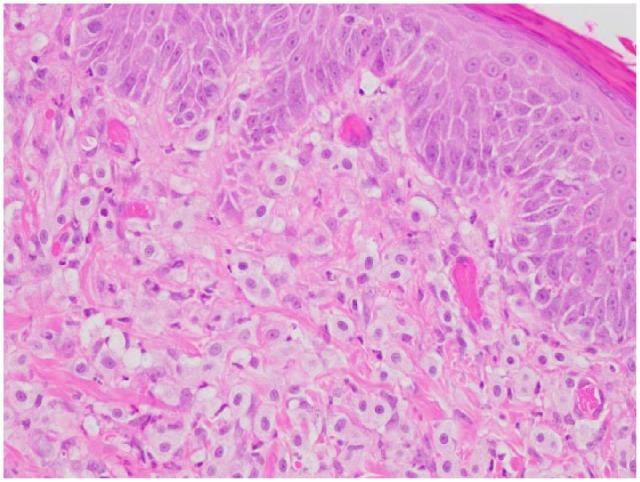

A 14-month-old castrated male domestic shorthair cat presented with an 8 month history of severe pruritus, alopecia, papules and excoriations. Initial evaluation and treatment prior to referral included skin scrape, cytology, two strict food trials, dermatophyte culture, and bacterial culture and sensitivity, as well as antibiotic therapy, empiric treatment for mites, steroids and ciclosporin A (Atopica; Elanco). The cat was referred to the Dermatology and Otology Clinic at the University of Illinois Veterinary Teaching Hospital for further diagnostics and treatment. Skin scrapes were unremarkable. Cytology showed rare bacteria and moderate neutrophils. The cat was given an injection of triamcinolone acetonide, which was ineffective. Oclacitinib (Apoquel; Zoetis) was given for 4 weeks with no improvement. A skin biopsy was performed, and histopathology showed large numbers of well-differentiated monomorphic mast cells with fewer eosinophils that diffusely infiltrated the superficial dermis, supportive of urticaria pigmentosa. Oral dexamethasone and cetirizine hydrochloride were initiated, and the cat responded favorably. At the time of writing, the cat continues to do well on cetirizine hydrochloride with only intermittent tapering courses of dexamethasone.

一只14个月大已绝育的雄性家猫出现严重瘙痒、脱毛、丘疹和抓痕8个月。转诊前的初步评估和治疗包括皮肤刮片、细胞学检查、两次严格的食物试验、皮肤真菌培养、细菌培养及药敏试验,以及抗生素治疗、经验性抗螨治疗、类固醇和环孢素A(爱波克;英特威)。这只猫被转诊至伊利诺伊大学兽医学院教学医院的皮肤科和耳科诊所进行进一步诊断和治疗。皮肤刮片检查未见异常。细胞学检查显示有少量细菌和中度嗜中性粒细胞。给这只猫注射了曲安奈德,但无效。给予奥克拉替尼(阿比可;硕腾)治疗4周,无改善。进行了皮肤活检,组织病理学显示大量分化良好的单形性肥大细胞,嗜酸性粒细胞较少,弥漫性浸润浅表真皮,支持色素性荨麻疹。开始口服地塞米松和盐酸西替利嗪,这只猫反应良好。在撰写本文时,这只猫继续服用盐酸西替利嗪,仅间歇性地逐渐减少地塞米松剂量,情况良好。